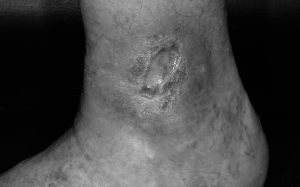

Chronische Wunde am Knöchel

04.09.2016